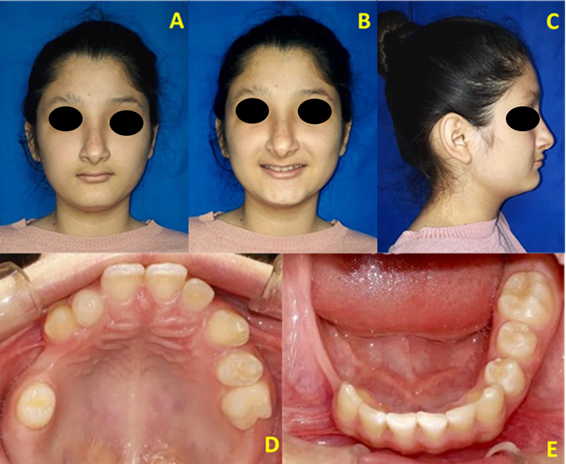

Her medical history did not relate harmful or pathological habits; however, in 2009 the Dermatology Service of the Central Air Force Hospital reported linear hyperpigmented lesions in the arms, limbs and nasal region; no ocular or nail alterations were observed. The overall assessment showed that she was a hemodynamically stable patient, with vital functions (blood pressure, pulse, respiratory rate and temperature) within normal values, and was also asymptomatic; scar lesions in the nasal region were observed in the current dermatological evaluation (Fig. 2A, 2B and 2C).

Fig. 2: A, B, (Atrophic lesions in the nasal region that occur cumulatively). C (Protruded chin, depressed malar region). D (Multiple missing teeth, morphological alterations and persistence of deciduous teeth). E (Thin alveolar ridge at the lower right area).